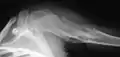

X-ray showing enchondromas localized in the humerus of a 37-year-old patient affected with Ollier disease

Enchondromas localized in the upper part of the humerus of the same patient